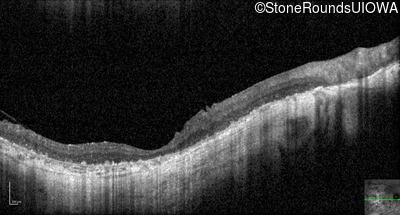

Optical Coherence Tomography - Right - Hand Motion

Exemplar / OCT Stack